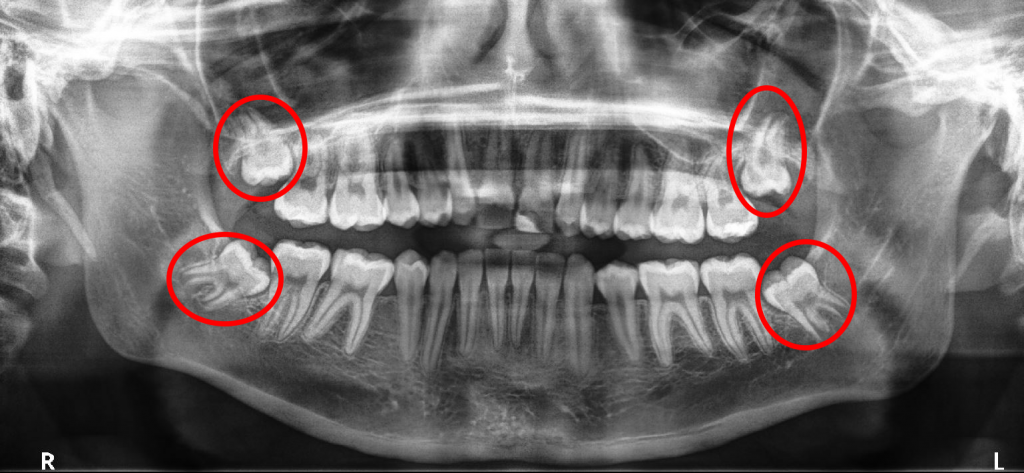

پیوند استخوان در ایمپلنت دندان

برای اینکه انواع روکش ایمپلنت بهخوبی در استخوان فک قرار بگیرد، باید حجم استخوان فک بازسازی شود؛ به همین دلیل جراحی پیوند استخوان انجام میشود. زمانی که استخوان کافی وجود نداشته باشد، ایمپلنت به فک متصل نشده یا در زمان کوتاهی شل میشود. اگر استخوان فک نازک یا ارتفاع آن کم باشد، پیوند استخوان در ایمپلنت دندان انجام میشود.

انواع پیوند استخوان در ایمپلنت دندان کدامند؟

اگر در قسمتی که دندان خود را از دست دادهاید، حجم و تراکم استخوان کم باشد، پیوند استخوان برای افزایش عمر ایمپلنت دندان انجام میشود. مواد پیوند استخوان را میتوان با روشهای مختلف تهیه کرد. برای پیوند استخوان در دهان از چه موادی استفاده می شود؟ انواع مواد پیوند شامل موارد زیر است:

عمل پیوند استخوان برای چه افرادی ضروری است؟

یا در واقع میتوان گفت که پیوند استخوان برای ایمپلنت برای چه کسانی مناسب است؟ هر شخصی که بخواهد کاشت ایمپلنت انجام دهد و حجم و تراکم استخوان فک پایینی داشته باشد، نیاز به پیوند استخوان دارد. ایمپلنت زیگوماتیک یکی از بهترین روشهای کاشت دندان برای افرادی است که استخوان آنها تحلیل رفته است. معمولا افراد با شرایط زیر نیاز به این جراحی دارند: